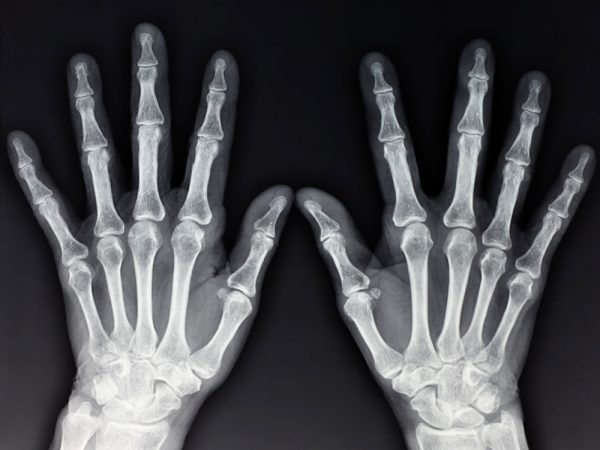

Doença que se caracteriza pelo desgaste da cartilagem articular e por alterações ósseas, entre elas os osteófitos, conhecidos vulgarmente como “bicos de papagaio”